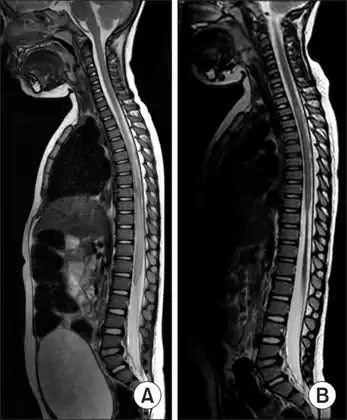

A proposed special presentation is the "longitudinally extensive transverse myelitis" (LETM), which is defined as a TM with a spinal cord lesion that extends over three or more vertebral segments.[15] The causes of LETM are also heterogeneous[16] and the presence of MOG auto-antibodies has been proposed as a biomarker for discrimination.[17]